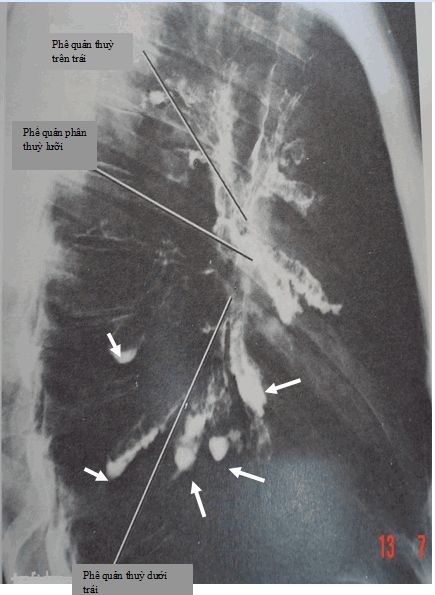

- Giãn phế quản hình trụ: phế quản được mở rộng và hình trụ.

Đường hô hấp bị ảnh hưởng đang viêm và dễ dàng suy yếu. Có sự giảm luồng không khí và thoát chất tiết, dẫn đến sự tích tụ số lượng lớn các chất nhầy trong phổi. Chất nhầy thu thập vi khuẩn, nguyên nhân nền để nhiễm trùng đường hô hấp dưới thường xuyên và thường nặng. Mức độ nghiêm trọng của chứng giãn phế quản thường được phân loại theo khối lượng đờm nhưng nay phần lớn được thay thế bằng sự xuất hiện dấu hiệu trên CT scan.